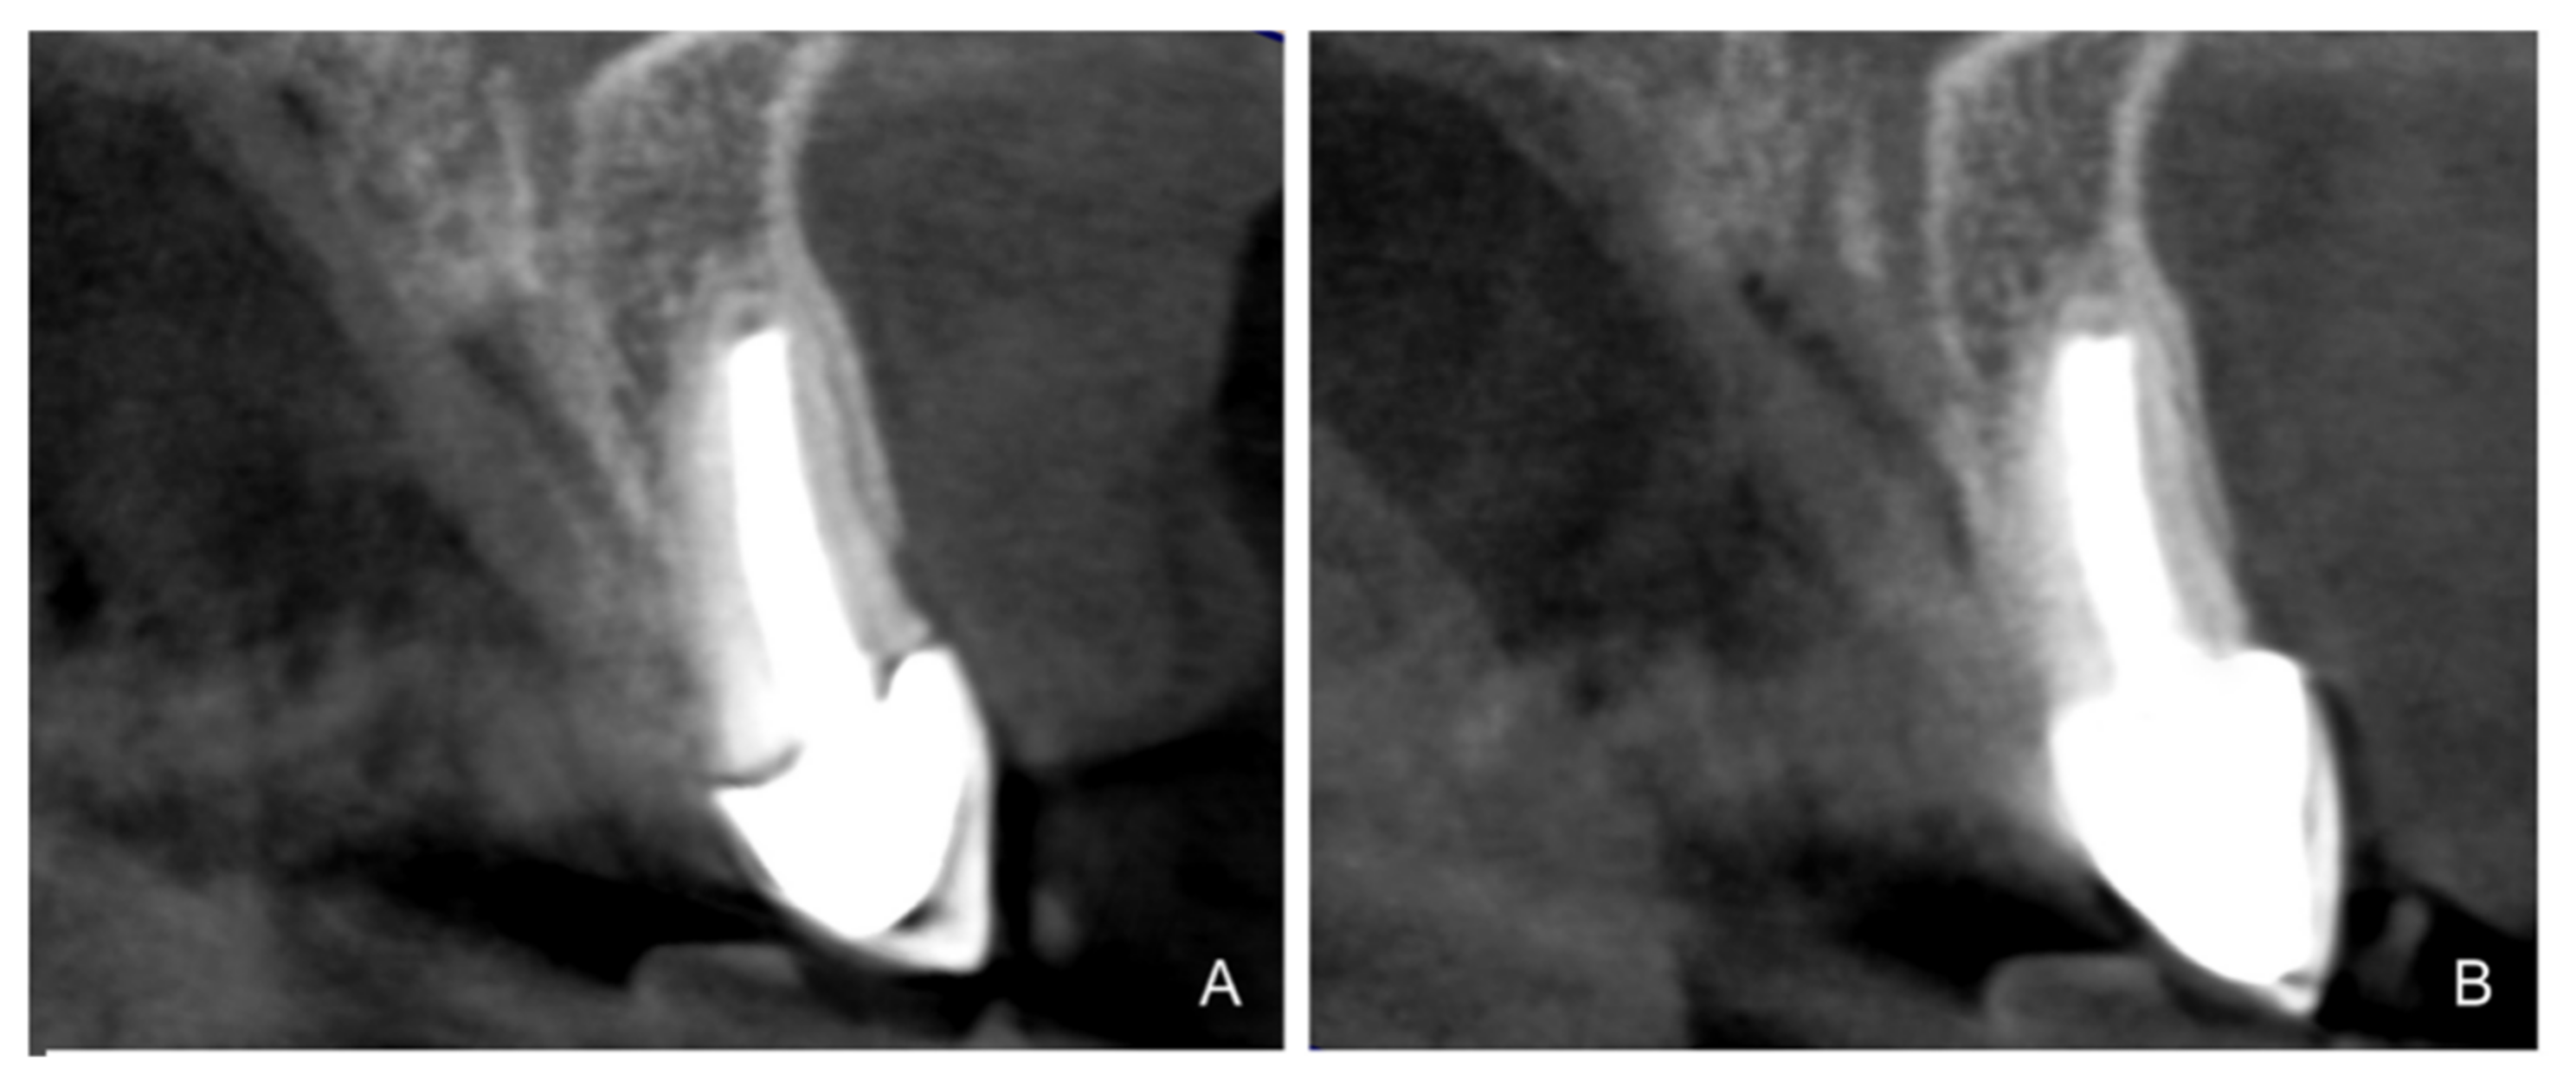

- Teeth treated with this technique presented improved plaque indices, stable probing depths, increased gingival thickness, and stable gingival margins over the 6-year follow-up.

- Treatment with a fixed prosthesis using the BOPT technique has a positive impact on patient satisfaction, especially in cases concerning the re-treatment of old fixed prostheses. This fact is due to the esthetic improvement not only of the restoration but also of the surrounding tissues, as it improves gingival quality by thickening the tissue, thus preventing gingival recession.

- On the basis of the results obtained, BOPT may be recommended in cases requiring re-treatment with prosthetic crowns.